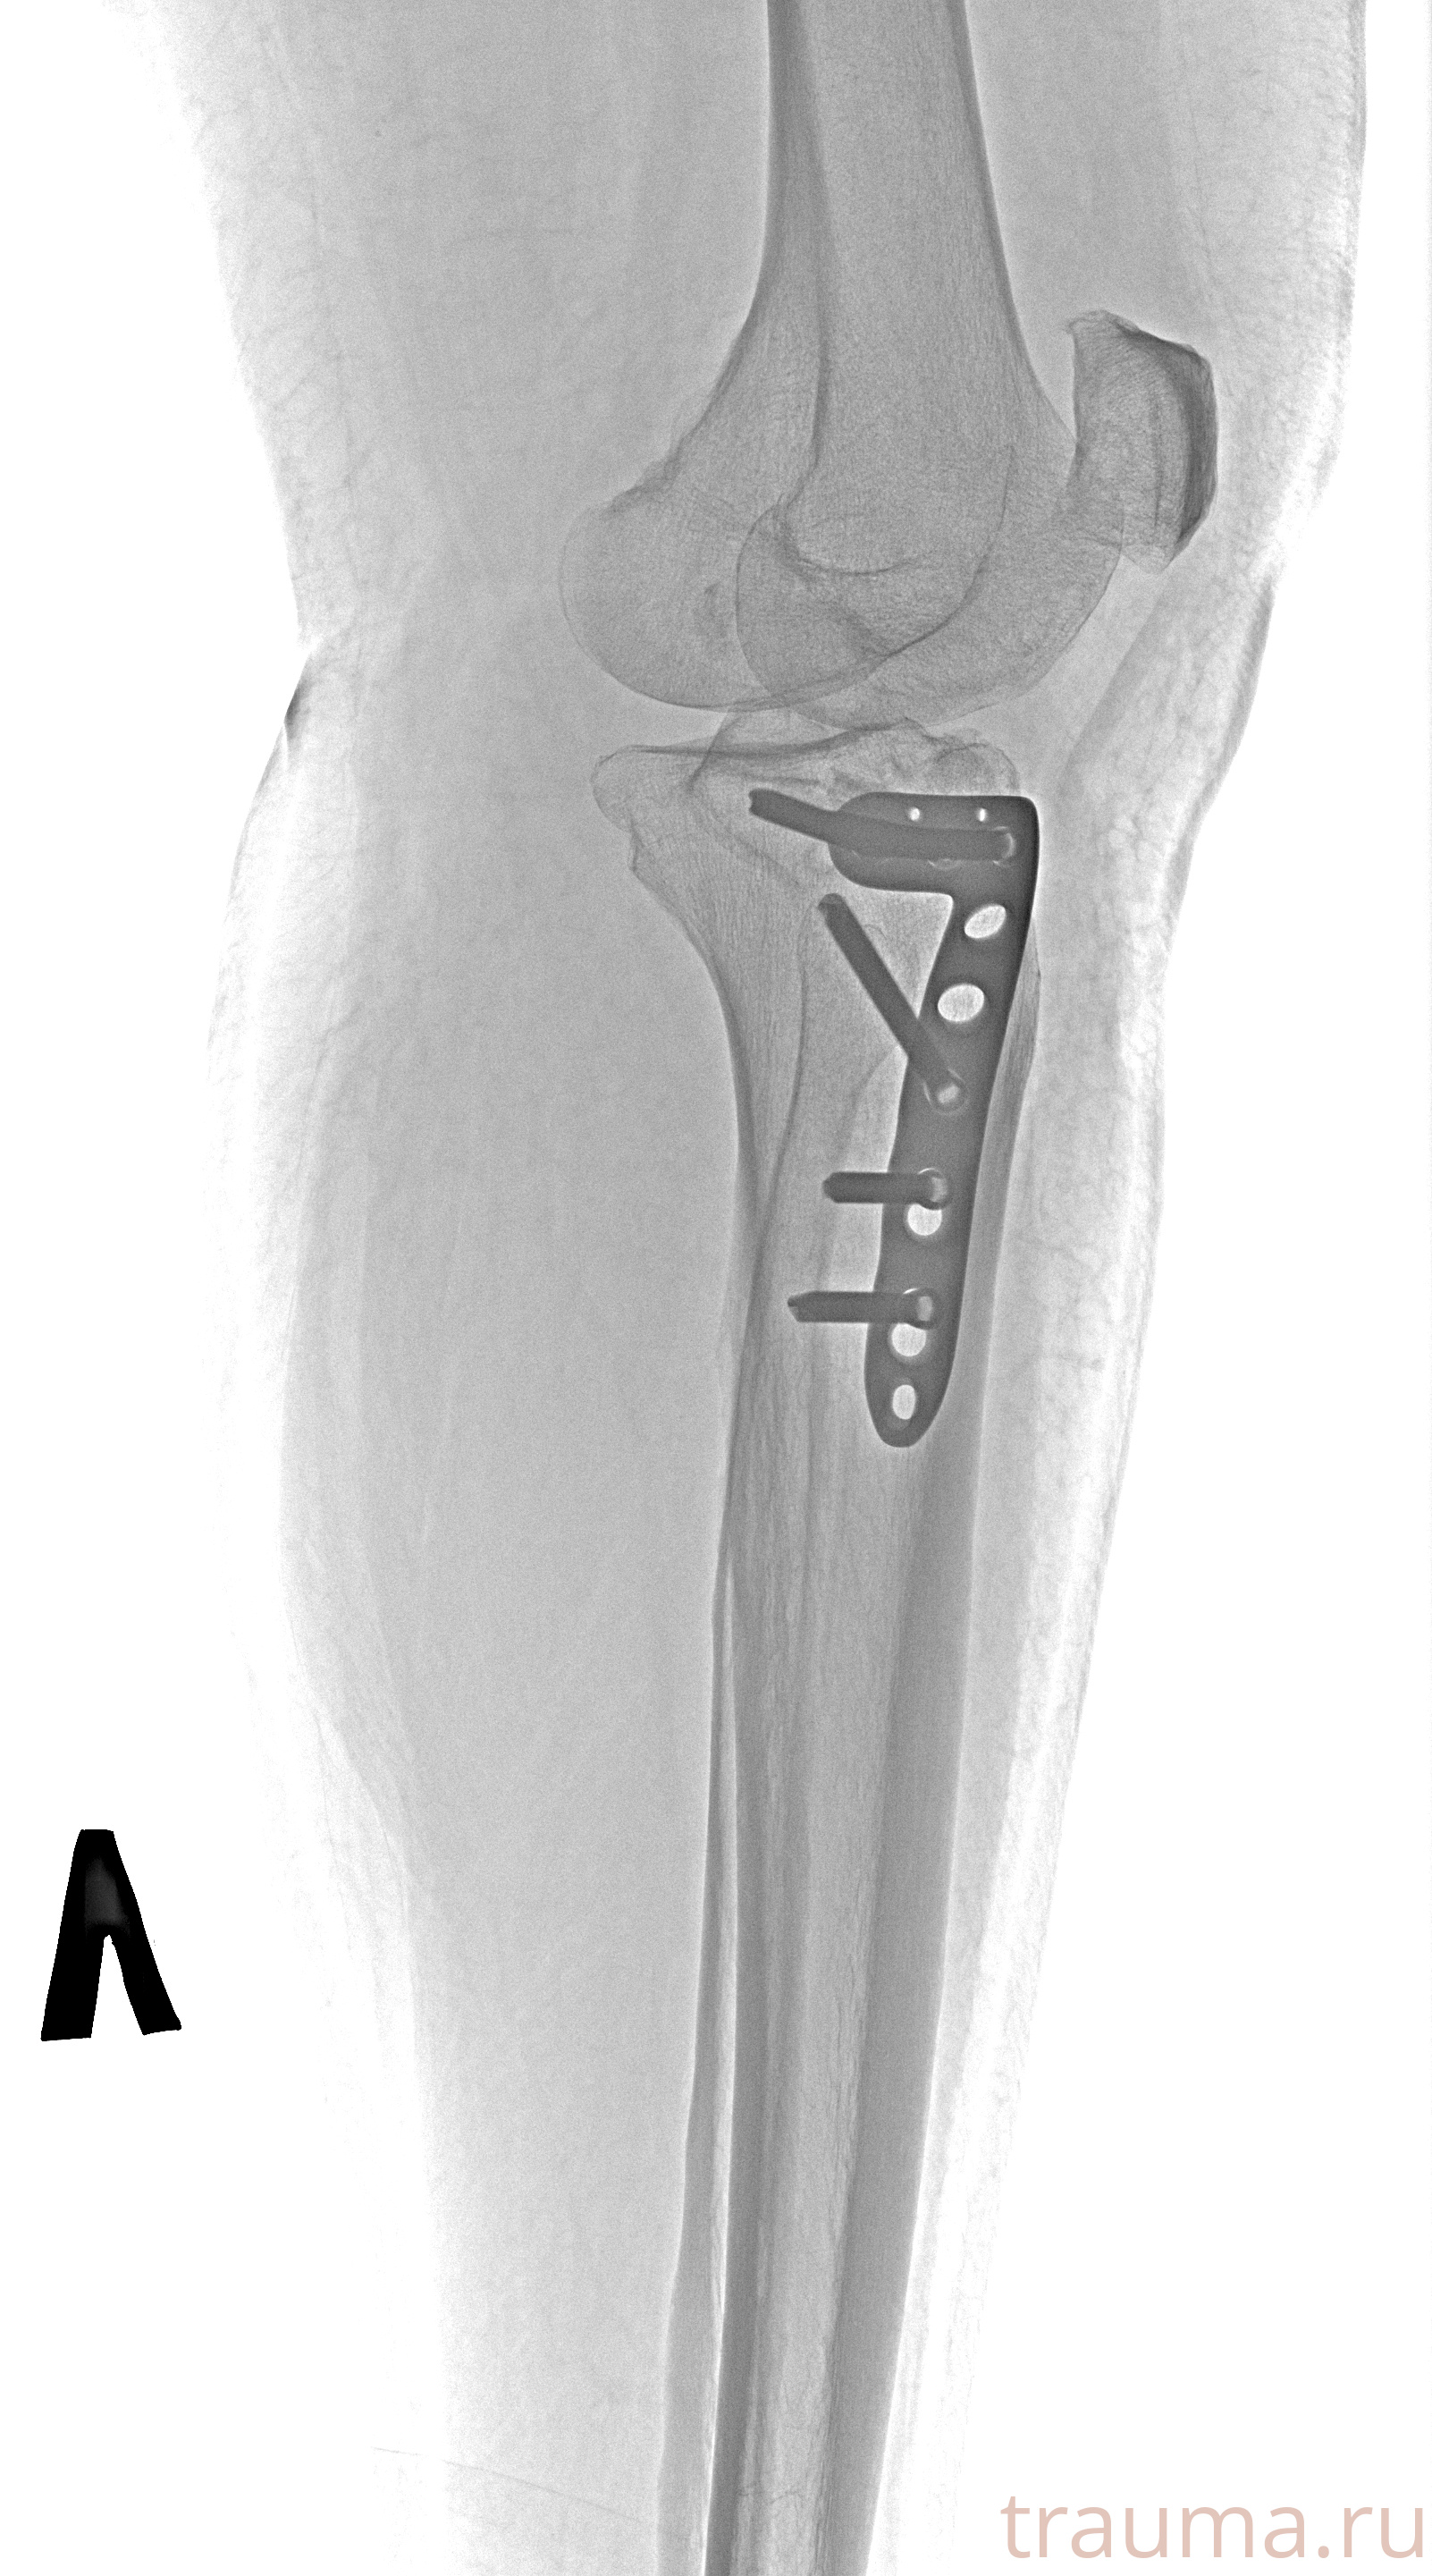

Рентгенограммы